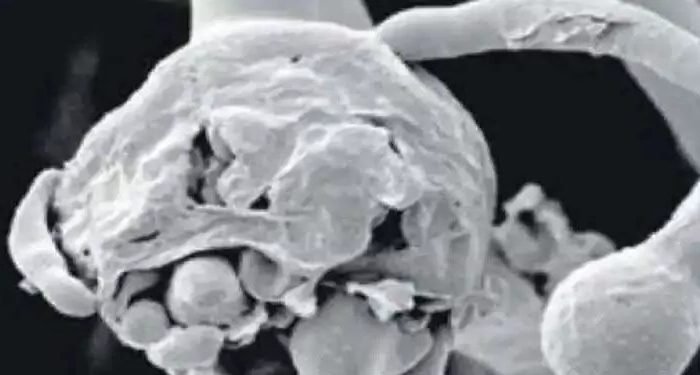

पीएमसीएच में माइक्रोबायोलॉजी विभाग के प्रमुख डॉ. एसएन सिंह के अनुसार अब तक ऐसे चार मरीज मिले हैं, जिनमें कोरोना जैसे लक्षण थे. हालांकि वह कोरोना नहीं बल्कि व्हाइट फंगस से संक्रमित थे. व्हाइट फंगस को मेडिकल टर्म में कैंडिडोसिस भी कहते हैं. ये बेहद खतरनाक है.

व्हाइट फंगस (कैंडिडोसिस) फेफड़ों के संक्रमण का मुख्य कारण है. फेफड़ों के अलावा, स्किन, नाखून, मुंह के अंदरूनी भाग, आमाशय और आंत, किडनी, गुप्तांग और ब्रेन आदि को भी संक्रमित करता है. इलाज में देर हुई तो फिर मरीजों की जान पर गंभीर संकट खडा हो जाता है.

व्हाइट फंगस द्वारा फेफड़ों के संक्रमण के लक्षण एचआरसीटी में कोरोना के लक्षणों जैसे ही दिखते हैं. जिसमें अंतर करना मुश्किल हो जाता है. इसलिए वैसे मरीजों में रैपिड एंटीजन और आरटी-पीसीआर नेगेटिव है.